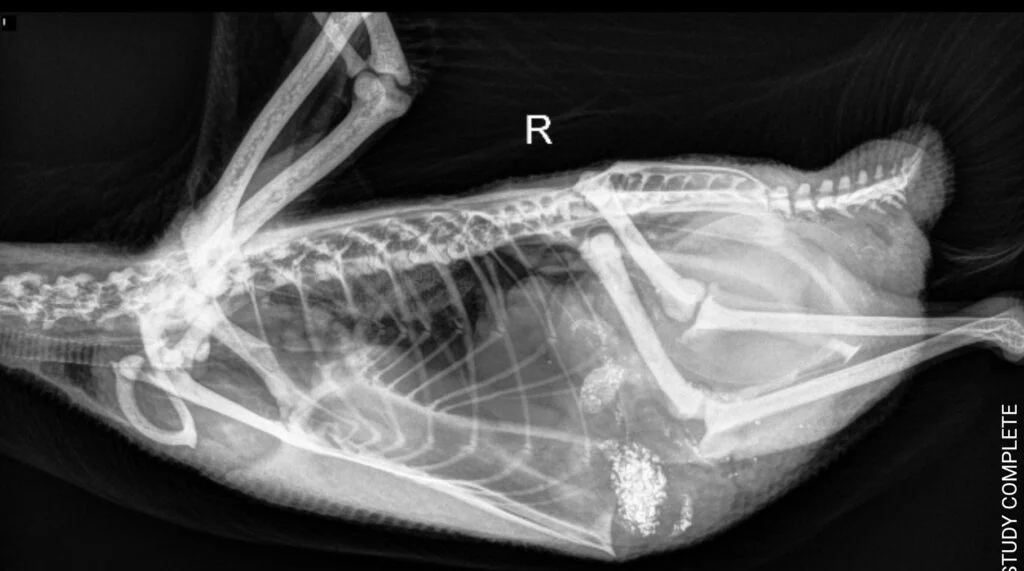

X-rays (Radiographs)

X-rays give your vet a visual look inside your duck’s body, especially useful for bones, reproductive organs, and the digestive tract.

Common reasons for X-rays:

- Suspected egg binding

- Prolapsed tissue

- Lameness or fractures

- Metal ingestion, such as screws or coins

💡 While metal sometimes doesn’t show up clearly (especially if small), X-rays can still guide decisions on treatment or surgery.